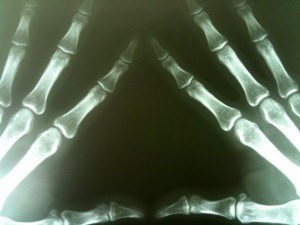

Films—such as x-rays and negatives—are sensitive to temperatures, relative humidity levels and water. X-rays have a base, or plastic backing, and emulsion. The emulsion toughens under light and makes the image more durable. Unlike true emulsions, those used for films are a suspension of solid particles in a gelatin solution. When a medical facility suffers water damage that affects films, x-ray restoration is critical to preserving valuable patient information.

[Photo from Michael Dorausch via CC License 2.0]